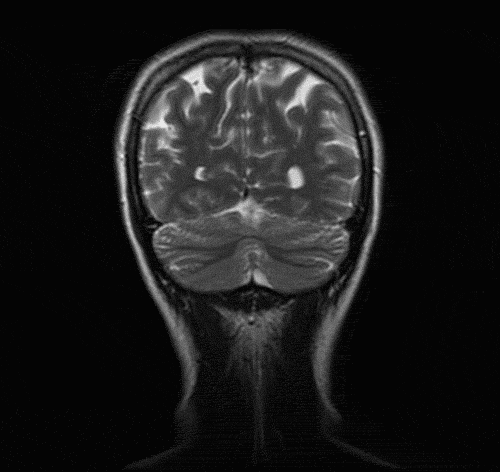

MRI of the Head

Neuroimaging of the Head